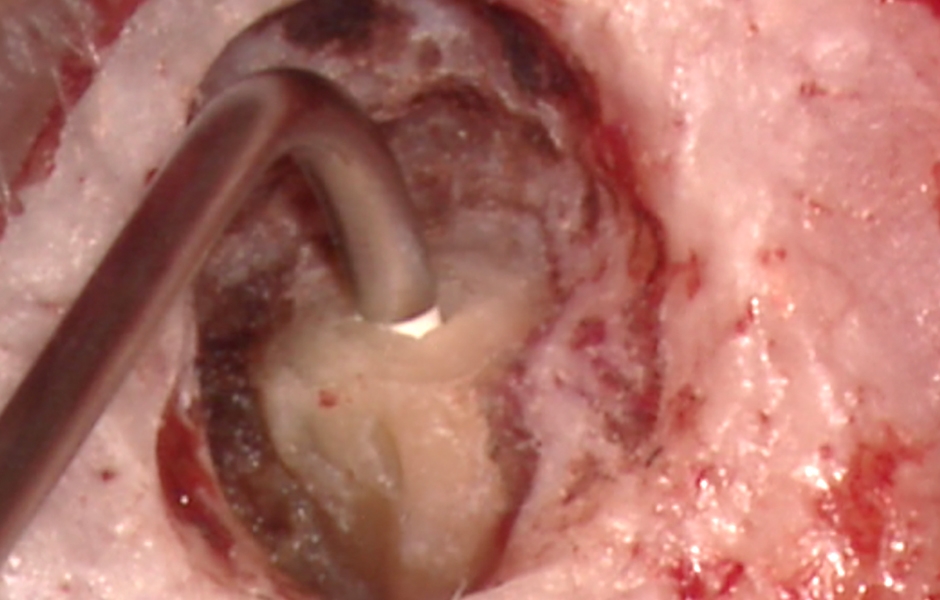

Obr. 2.4: Zavedení sondy do ústí laterálního kanálku odpovědného za laterální lézi.

Obr. 2.5: Ultrazvukový nástroj při preparaci dutiny v hlavním kořenovém kanálku.

Obr. 4.3: Retrográdní výplň MB1, MB2 a isthmu.